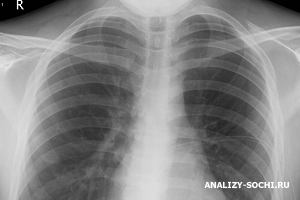

В диагностике силикоза ведущую роль играет рентгенологический метод исследования. В рентгенологической классификации выделяют малые и большие затемнения. Исходя из рентгенологической характеристики выделяют интерстициальную, узелковую и узловую форму силикоза.

При силикозе может использоваться также компьютерная томография легких с высоким разрешением, которая используется в тех случаях, когда изменения на рентгенограммах грудной клетки незначительны, а данные физикального исследования свидетельствуют о поражении легких.

Силикоз приходится дифференцировать главным образом от диссеминированного туберкулеза. При туберкулезе туберкулезные очажки на рентгенограммах характеризуются полиморфизмом, нечеткостью контуров, различной величиной и плотностью, а также преимущественной локализацией в верхних отделах легких.